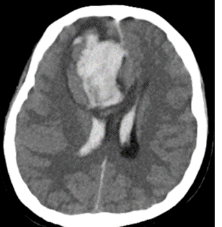

▲急诊头颅CT正侧位图显示患者颅内大量出血

患者病情危急,行急诊手术前须完成一些关键必要的检查如头颅CT扫描等。为提高效率,专家们充分利用送检时间同步会诊。当患者被送进手术室时,最可行的手术方案和目标正好出炉:神经外科开颅血肿清除减压术和产科剖宫产术同时同台进行,麻醉科、手术室和新生儿科在手术室全程充分协作、监护和保障,重症医学科随时做好该孕产妇围手术期各种应急处置准备。